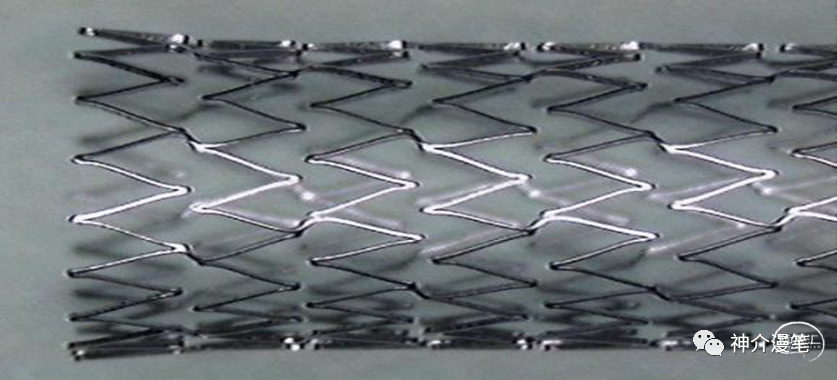

第一个概念:开环支架与闭环支架。开环支架有自己独立的支架单元,每个单元之间有少数几个连接点相连,这样能保证每一个支架单元的相对独立性。在弯曲迂曲,管径差异较大的血管条件下能保持更好的贴壁性。下图即为典型的开环支架设计,红色部分为支架单元之间的连接点,其余部分呈现为开放不连续状态。

下图为开环支架打开及释放的过程,可以看到每一环支架都会相对独立,而不会过多的影响其他部位打开的情况。所以对于好多新手,我会建议他们早期可以尝试开环支架的释放,因为头端一旦打开就会有比较良好的贴壁性,而不用担心支架滑落。